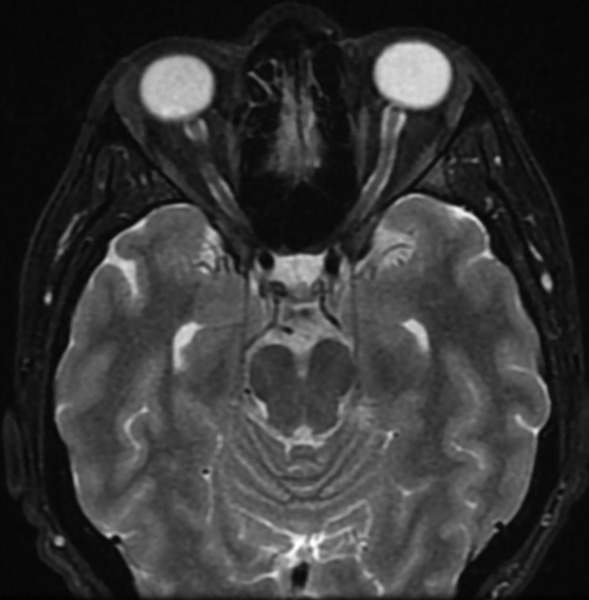

W badaniu neurologicznym wykonanym przy przyjęciu na oddział nie stwierdzono odchyleń od stanu prawidłowego, poza zgłaszanym przez pacjentkę dwojeniem przy spojrzeniu na wprost i w prawo. Wykonano rezonans magnetyczny (MR) głowy z kontrastem, który wykazał objaw częściowo pustego siodła tureckiego (ryc. 1). W MR odcinka szyjnego kręgosłupa uwidoczniono cechy umiarkowanej spondylozy szyjnej, bez zmian pourazowych. W rezonansie magnetycznym oczodołów wykazano natomiast cechy nadciśnienia śródczaszkowego pod postacią zwiększonej ilości płynu w pochewkach nerwów wzrokowych oraz obrzęku tarcz, z poszerzeniem zbiornika nadsiodłowego (ryc. 2, 3).

Rycina 1. Rezonans magnetyczny 3D T2 CUBE FLAIR w płaszczyznach strzałkowych – powiększony zbiornik nadsiodłowy